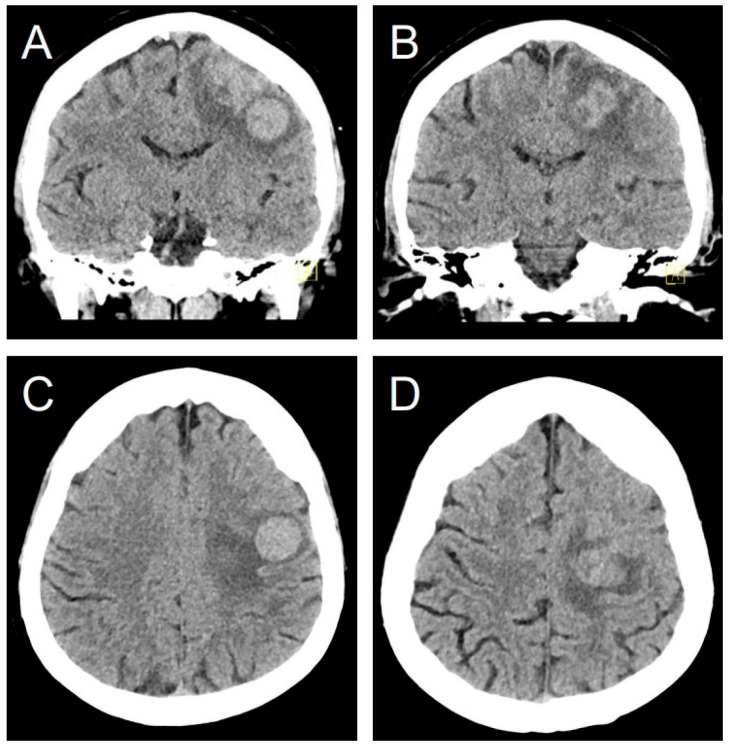

背景/目的:子宫平滑肌肉瘤(ULMS)脑转移是一种罕见的侵袭性恶性肿瘤并发症。由于以前记录的病例不到40例,因此在其临床过程、管理和结果方面存在显著的知识差距。这项研究提供了迄今为止最大的ULMS脑转移分析,整合了系统的文献综述和一个新的病例报告,说明了该疾病独特的快速进展。方法:遵循PRISMA指南,我们系统地回顾了四个主要数据库,以确定所有报告的ULMS颅内转移病例。提取和分析患者人口统计学、临床放射学特征、治疗和生存数据。采用改进的乔安娜布里格斯研究所(JBI)工具评估方法学质量。结果:我们分析了34项研究和39例个体病例。此外,本综述还补充了来自我们机构的一个新的说明性案例。患者中位年龄为51.5岁,多数表现为局灶性神经症状。常见的影像学表现包括CT上的高密度病变和MRI上均匀增强的硬脑膜基础肿块,类似于其他颅内病变。虽然手术是最常见的干预措施(76.9%),但脑转移诊断后的中位生存期为严峻的5个月,治疗方式之间没有显著差异。我们的例子非常引人注目,它的体积翻倍时间非常快,平均只有7.3天。结论:ULMS脑转移是一种预后极差的致命事件。非特异性影像学特征造成诊断困难,需要组织病理学证实。目前的治疗方法,包括手术和放疗,提供了姑息性的好处,但没有显著改变生存。这里展示的侵略性生物学行为强调了迫切需要提高临床意识和合作研究,以制定更有效的管理策略并改善这种毁灭性诊断的结果。

Background/Objectives: Brain metastasis from uterine leiomyosarcoma (ULMS) is an exceptionally rare complication of an aggressive malignancy. With fewer than 40 cases previously documented, a significant knowledge gap exists regarding its clinical course, management, and outcomes. This study provides the largest analysis of ULMS brain metastases to date, integrating a systematic literature review with a novel case report illustrating the disease's uniquely rapid progression. Methods: Following PRISMA guidelines, we systematically reviewed four major databases to identify all reported cases of intracranial metastasis from ULMS. Data on patient demographics, clinico-radiological features, treatments, and survival were extracted and analyzed. Methodological quality was assessed using a modified Joanna Briggs Institute (JBI) tool. Results: We analyzed 34 studies with 39 individual cases. Additionally, this review was supplemented by one new illustrative case from our institution. The median patient age was 51.5 years, and most presented with focal neurological symptoms. Common imaging findings included hyperdense lesions on CT and homogeneously enhancing, dural-based masses on MRI, which mimic other intracranial pathologies. Though surgery was the most frequent intervention (76.9%), median survival after a brain metastasis diagnosis was a grim 5 months, with no significant difference observed between treatment modalities. Our illustrative case was remarkable for an extremely rapid volumetric doubling time averaging just 7.3 days. Conclusions: Brain metastasis from ULMS is a lethal event with an extremely poor prognosis. Nonspecific imaging features create diagnostic challenges, necessitating histopathological confirmation. Current therapies, including surgery and radiotherapy, offer palliative benefit but do not significantly alter survival. The aggressive biological behavior demonstrated here underscores the urgent need for increased clinical awareness and collaborative research to develop more effective management strategies and improve outcomes for this devastating diagnosis.